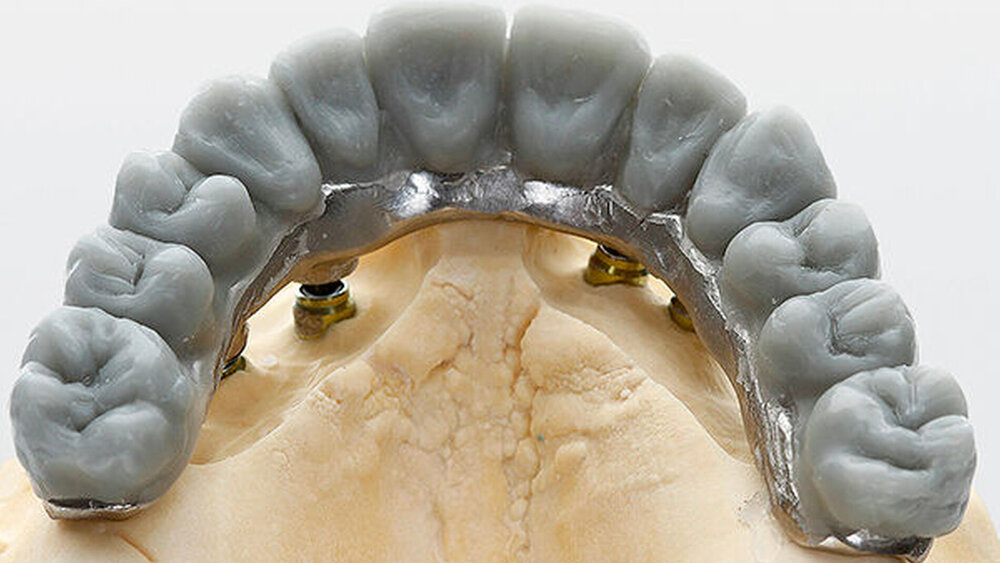

Die dreidimensionale Positionierung und die richtige Anordnung der Implantate sowie des Zahnersatzes. Es ist wichtig, eine prächirurgische prothetische An- und Sprechprobe (Set-up) durchzuführen, um die Implantatpositionen und -achsen korrekt nach der späteren Prothetik zu bestimmen und auszurichten.

Auch mit CAMLOG- oder CONELOG-Implantaten. Denn allein das individuell vom Zahntechniker oder von DEDICAM gefräste Provisorium für die fest verschraubte Sofortversorgung kann finanziell aufwendig werden. Dazu kommt noch die längere Planungszeit am Computer, im Labor und im Fräszentrum. Der implantatchirurgische Eingriff mit anschließender Sofortbelastung und Einbau eines direkt verschraubten Provisoriums birgt zudem Risiken und kostet Zeit bei Behandler und Zahntechniker.

Nein, aber das ist möglich. ZTM Stefan Picha hat die prothetische Versorgung übernommen.